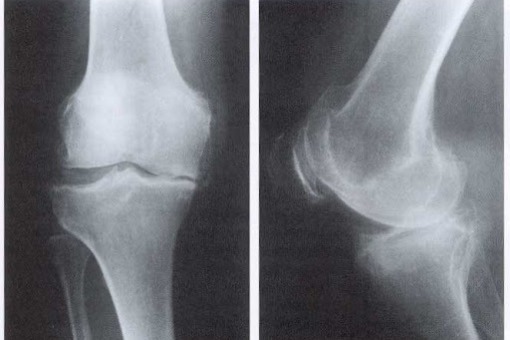

Choroba zwyrodnieniowa stawów jest jedną z najczęstszych chorób występujących wśród starszych pacjentów. Na łamach Arthritis Care & Research opublikowano przegląd systematyczny z meta-analizą badań obserwacyjnych dotyczących współwystępowania chorób w grupie pacjentów z chorobą zwyrodnieniową stawów.

Badacze w sumie zidentyfikowali 42 badania z 16 krajów. U 67% pacjentów z chorobą zwyrodnieniową stawów występowała jeszcze co najmniej jedna choroba, podczas gdy w przypadku rówieśników bez choroby zwyrodnieniowej stawów częstość ta wynosiła 56%. Co ważne, występowanie choroby zwyrodnieniowej stawów było związane z częstszym występowaniem dwóch, trzech lub więcej chorób. W porównaniu do osób bez choroby zwyrodnieniowej stawów, pacjenci z CHZS częściej cierpieli z powodu udaru mózgu (PR=2,61; 95% CI: 2,13–3,21), choroby wrzodowej żołądka (PR=2,36; 95% CI: 1,71–3,27) oraz zespołu metabolicznego (PR=1,94; 95% CI; 1,21–3,12).

Pacjenci cierpiący z powodu choroby zwyrodnieniowej stawów mają większe szanse na współwystępowanie innych przewlekłych chorób. Może to być wynikiem wspólnych czynników ryzyka (np. otyłości, jak w przypadku zespołu metabolicznego) lub powikłania leczenia choroby zwyrodnieniowej stawów (np. choroba wrzodowa żołądka w wyniku nadużywania niesteroidowych leków przeciwzapalnych).